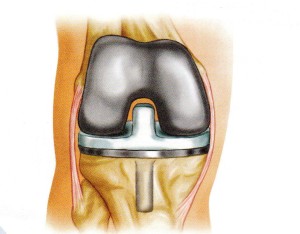

After years of legal maneuvering and court proceedings, the plaintiffs who filed product liability lawsuits against Zimmer Biomet regarding the defendant’s NexGen knee implant have agreed to a settlement arrangement. The news will likely be a huge relief to these plaintiffs, who have been waiting... Read More